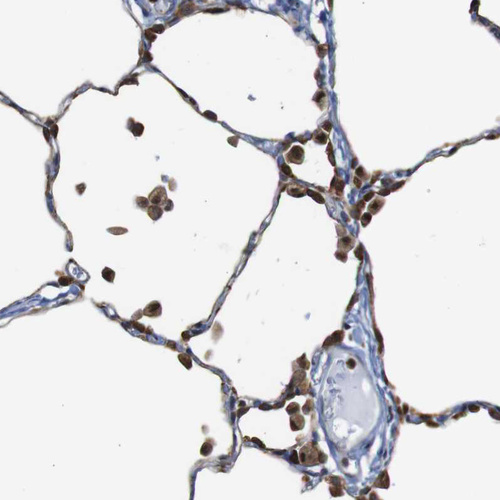

Immunohistochemical staining of human lymph node shows moderate to strong cytoplasmic positivity in non-germinal center cells.